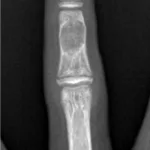

さらに, 昨日後輩医師の執刀で手術が行われた患者さん二人(膝外側半月板損傷に対する関節鏡下半月板縫合術, 変形性膝関節症に対する脛骨近位骨切り術後の骨内異物除去術)の経過を確認.